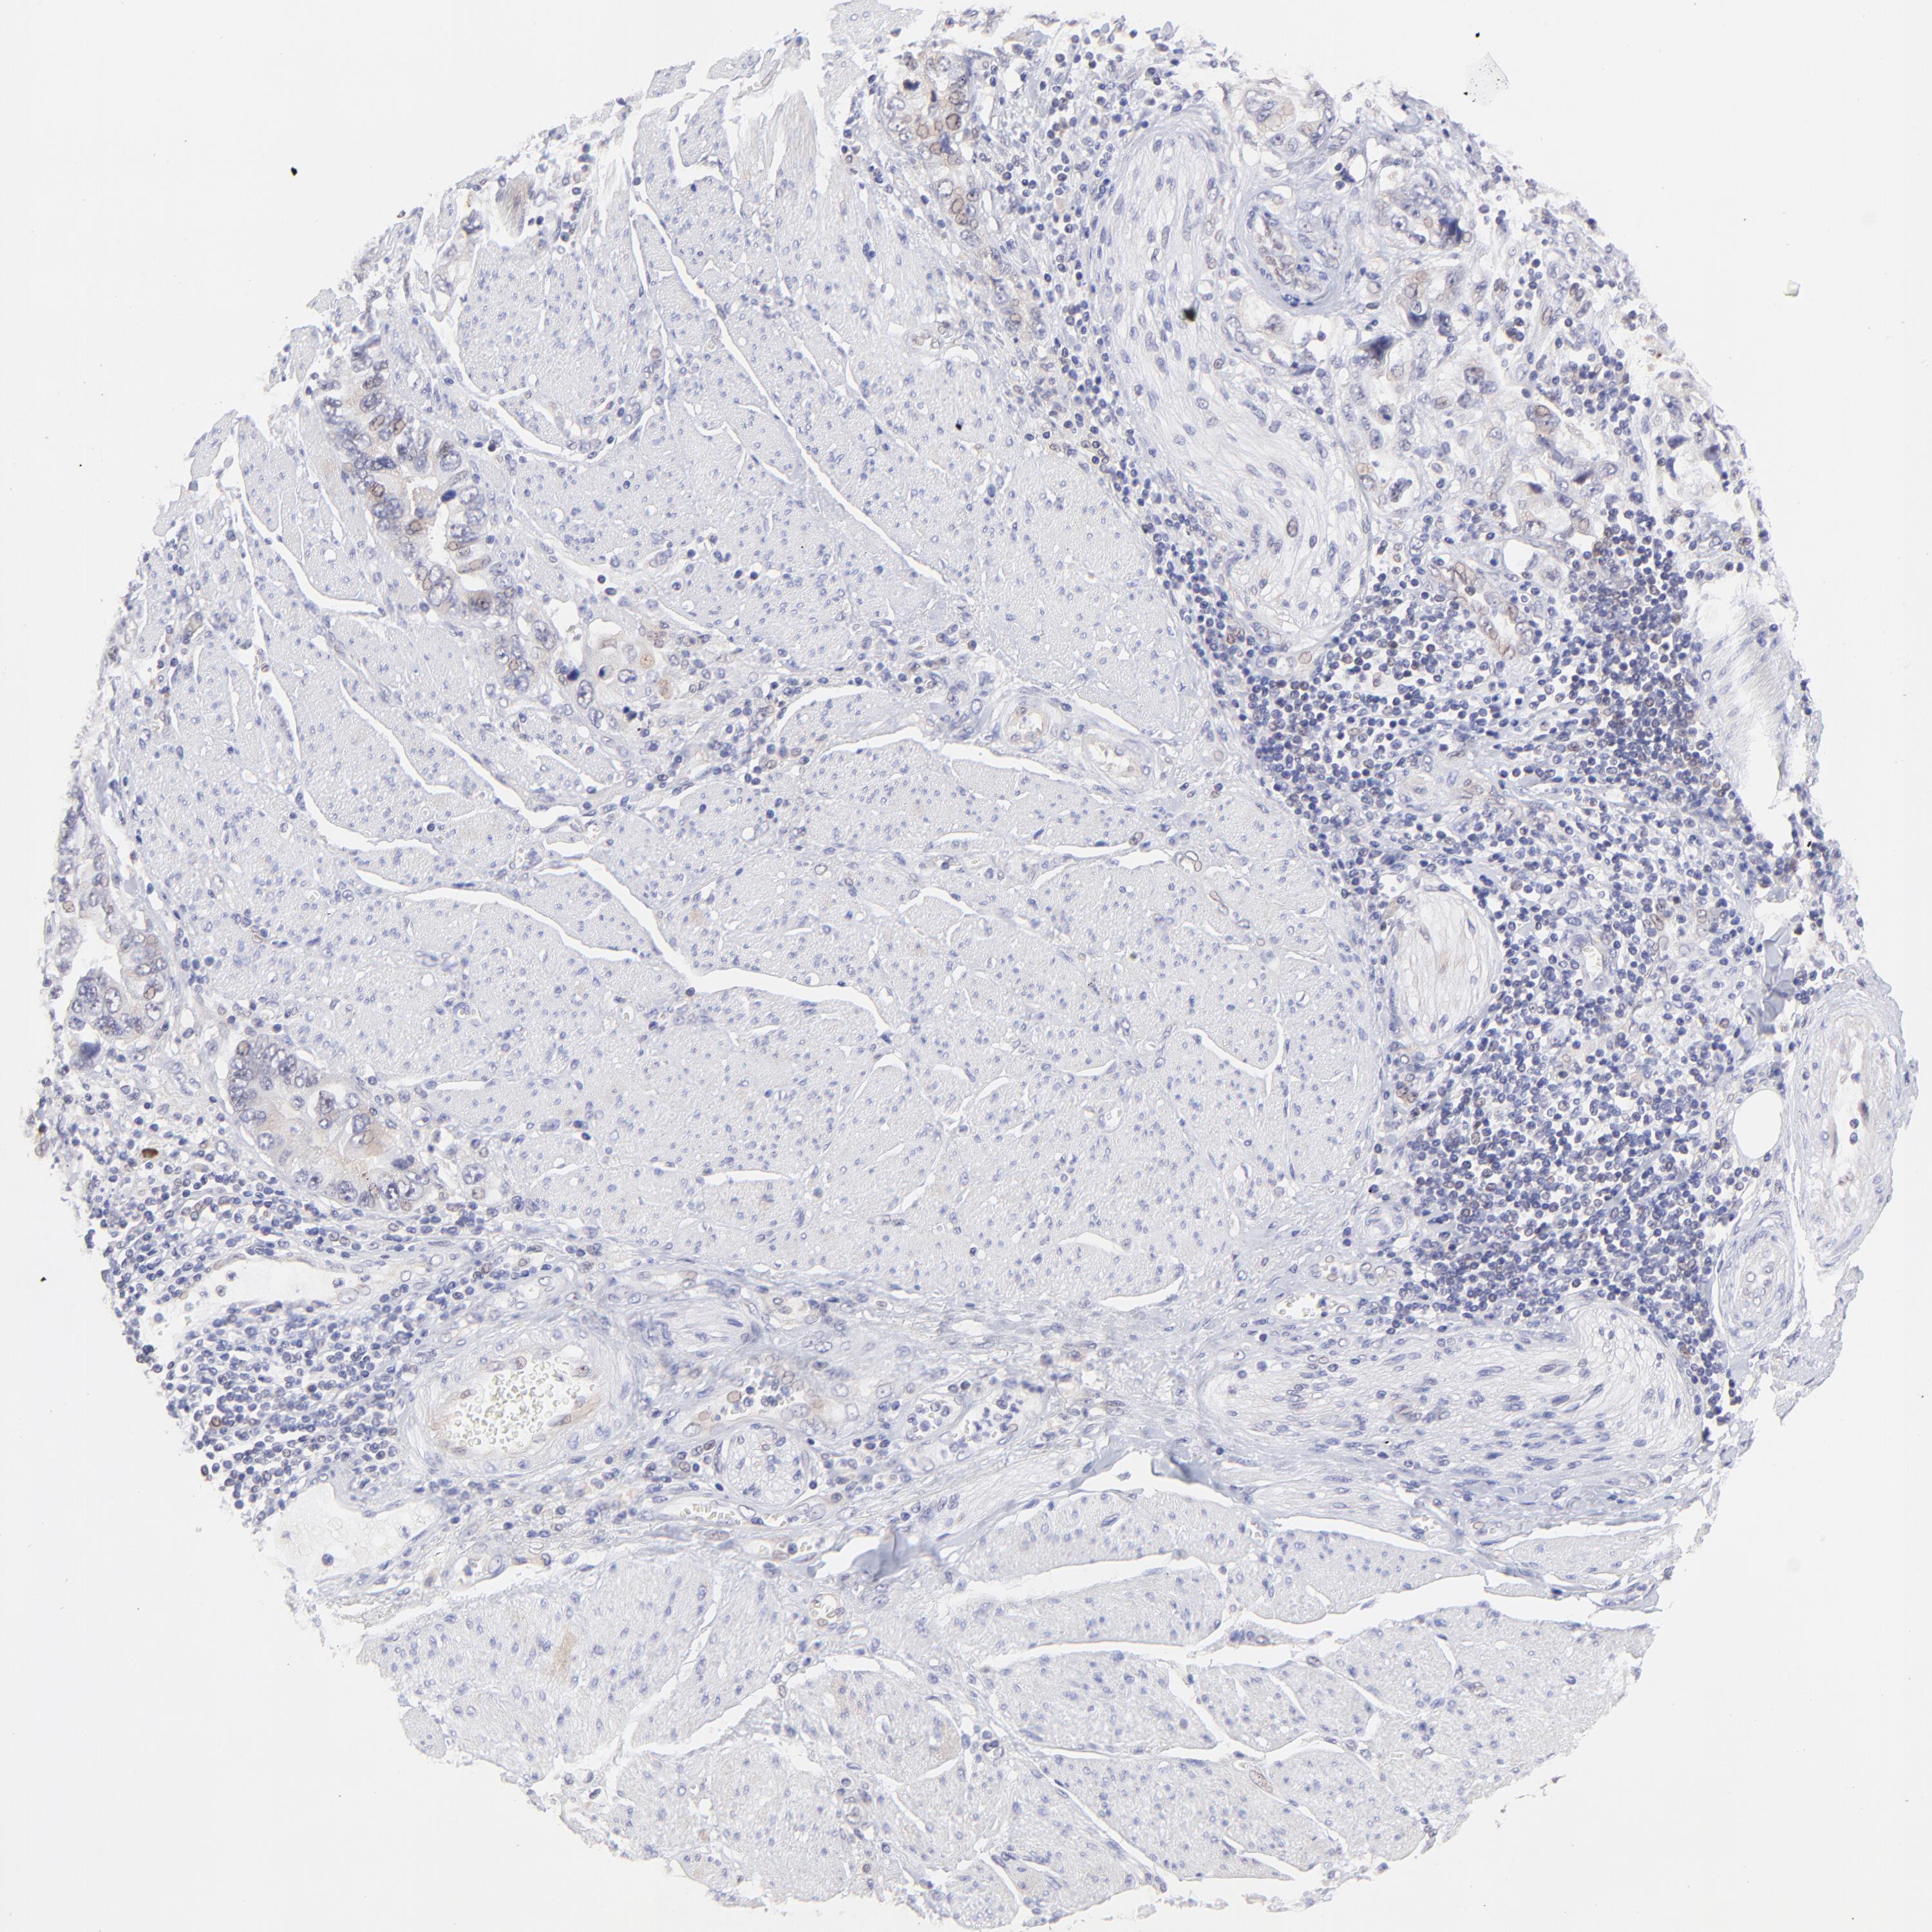

STOMACH CANCER - Protein expressioni

A mouse-over function shows sample information and annotation data. Click on an image to view it in a full screen mode. Samples can be filtered based on level of antibody staining by selecting one or several of the following categories: high, medium, low and not detected. The assay and annotation is described here.

Note that samples used for immunohistochemistry by the Human Protein Atlas do not correspond to samples in the TCGA dataset.

Antibody stainingi

Antibody staining in the annotated cell types in the current human tissue is reported as not detected, low, medium, or high, based on conventional immunohistochemistry profiling in selected tissues. This score is based on the combination of the staining intensity and fraction of stained cells.

Each image is clickable and will lead to virtual microscopy that enables deeper exploration of all samples and also displays staining intensity scores, fraction scores and subcellular localization as well as patient and tissue information for each sample.

Antibody HPA002112

Staining

High

Medium

Low

Not detected

Intensity

Strong

Moderate

Weak

Negative

Quantity

>75%

75%-25%

<25%

None

Location

Nuclear

Cytoplasmic/membranous

Cytoplasmic/membranous,nuclear

Adenocarcinoma, NOS